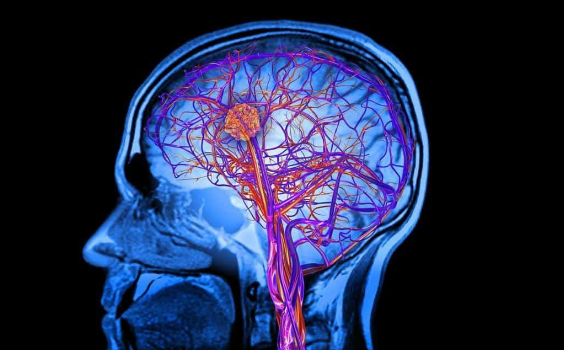

У магнітно-резонансної ангіографії довга історія. Відкриття в 1895 році Рентгеном нового виду випромінювання